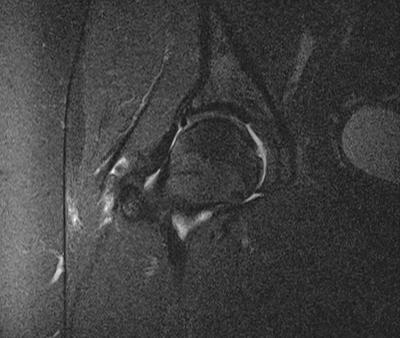

lumbar spine with L5 - pars defect

Referred to spinal surgeon - Pars defect L5? (see pic). Seems relatively stable, but wants to do nerve block/spinal injection into the pars to check. In the meantime, recently sat forward to pick something up off floor and had sudden severe 'burst/pop' in lower right groin area - great pain for about 1 hour after. Then right hip seemed to move more freely and less pain than before. Next day, better too. Then pain getting worse again over the following days. Now on max painkillers 8 x cocodamol 8/500 and 3 x diclofenac daily, but pain in groin.